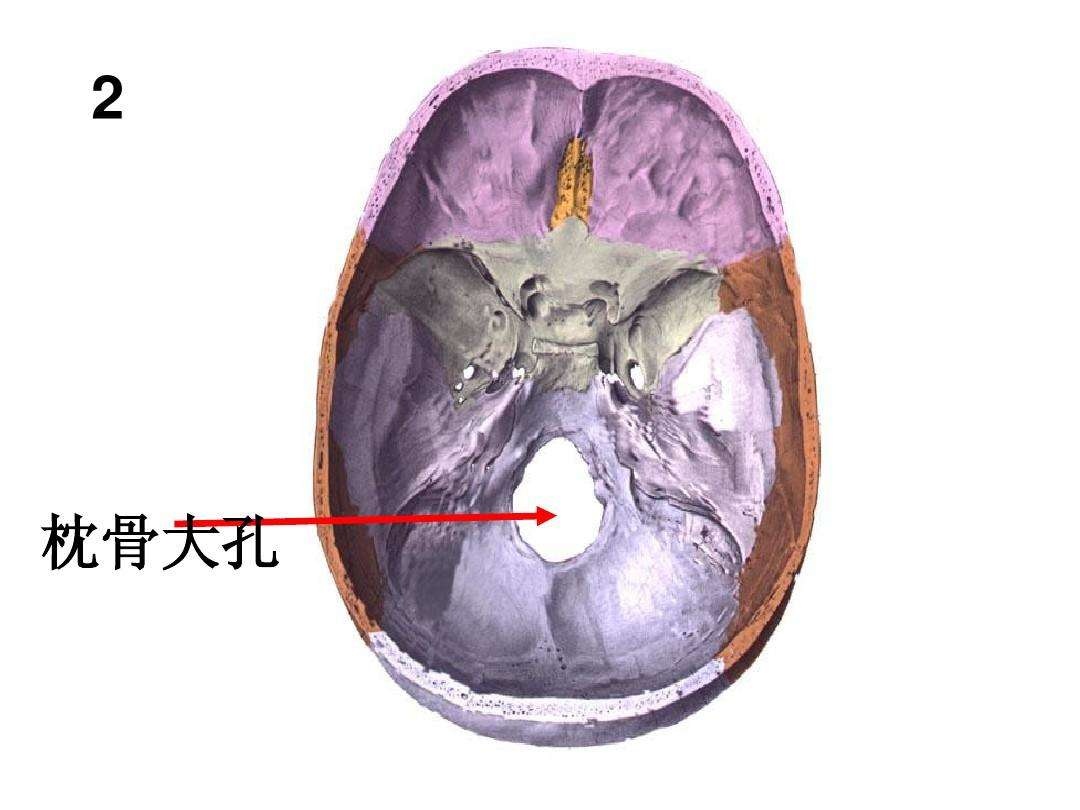

系统解剖实验的幻灯片 枕骨大孔

枕骨大孔ct解剖图

颅内疝包括:大脑镰下疝,中心疝,海马钩回疝,小脑扁桃体下疝.

血管及脑神经等重要结构受压和移位,被挤入硬脑膜的裂隙或枕骨大孔